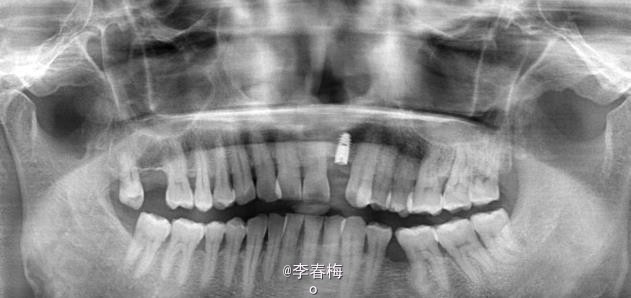

上颌前牙种植修复

患者,男,左上颌侧切牙缺失来诊。平素体质一般,无药物、食物过敏史,无高血压、心脏病等系统性疾病。